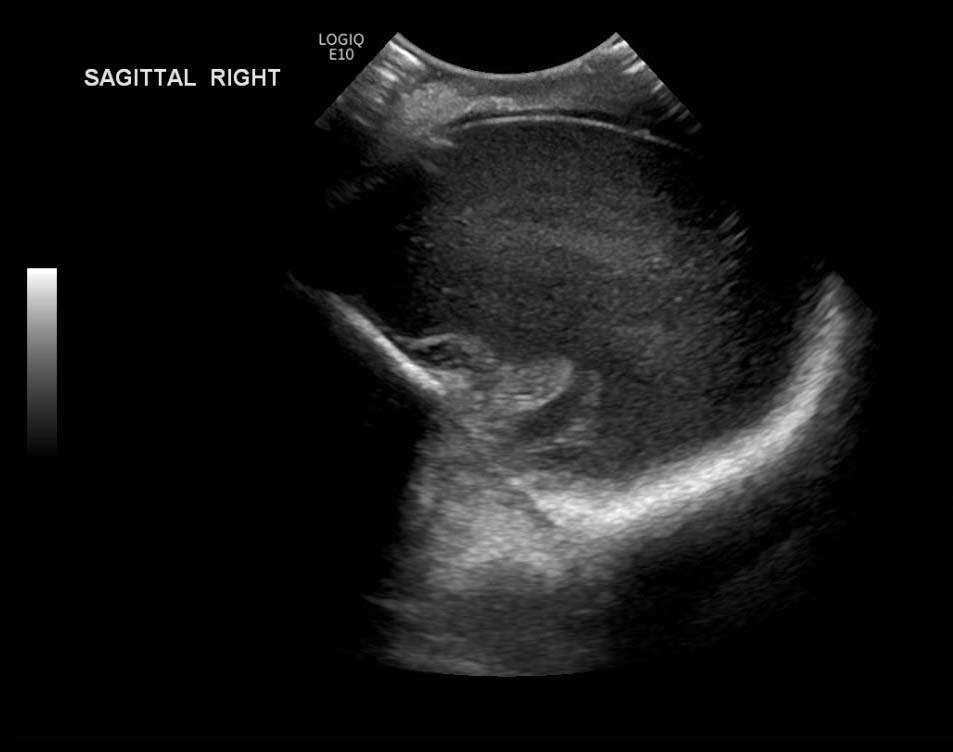

Age: 4 days (born at 24 weeks)

Sex: Male

Indication: Evaluate for germinal matrix hemorrhage

Grade 2 germinal matrix hemorrhage

Sample ReportLeft germinal matrix hemorrhage involving the caudothalamic groove and layering in the occipital horn of the left lateral ventricle without hydrocephalus (grade 2).

No abnormal brain parenchymal echogenicity or extra-axial collections.

Premature sulcation pattern.